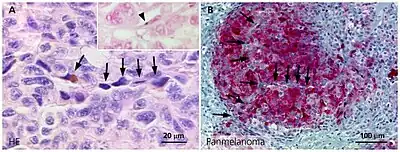

Clinically, VM is diagnosed through immunohistochemistry (IHC) and Periodic acid-Schiff stain (PAS) of patient tumor biopsy. IHC staining identifies the expression of common biomarkers of endothelial cells such as CD31, while PAS staining marks the extracellular matrix for glycoproteins, laminin, proteoglycans, heparin sulfate and collagens, which are known to be a sign of VM.[2] Clinicians diagnose a tumor as having VM by CD31-/PAS+ expressing blood conducting vessels, indicating that there are no endothelial cells but still vasculature present.[2][3]

Vascular mimicry may be divided into tubular and patterned matrix types.[9][3] Tubular VM is characterized by channels surrounded by glycoprotein covered tumor cells where endothelial cells would normally sit. Patterned matrix type VM lacks the endothelial-like tumor cells and is instead tumor cells that are enveloped by PAS+ matrix/